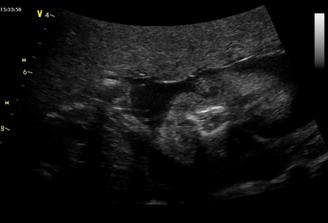

Panu doktorovi se nelíbily mozkové komory našeho broučka, že jsou moc velké, tak si nás pozval k Apolináři hned na druhý den. Tak to konzultoval ještě s kolegou, kterému se to taky nezdálo a ani nenašli část mozku- spojnici mezi dvěma hemisférami....proto hned mažeme na magnetickou rezonanci...40 minut si s Tobíkem "užíváme" tunelu a doufáme, že vše bude OK...ale bohužel dobré zprávy nepřišly...MR nezobrazila to, co by měla...jsme poslaní na genetiku, já brečím jak želva a jsem v šoku. Paní doktorka je moc milá, snaží se nám vše vysvětlit, ale její verdikt, že je to tak 50/50 - zdravé/postižené dítě mne děsí...vždyť je to 1:1!!!!! Po domluvě a doporučení se objednáváme na AMC, v lepším případě na odběr pupečníkové krve....

15.10.- další kontrolní UZUZ nedopadl moc dobře, komory se zvětšily na 16 mm...bohužel doktoři nedokážou nic víc k tomu říct...jen že to není dobré, ale ještě není nic ztraceno...další UZ 5.11.- Tak zas pár milimetrů nárůst (na 19 mm)...co to přinese? Bůh ví...další UZ 26.11....pak už asi kontroly v porodnici, kde budu rodit - v Motole. Komory si rostou dále jak chtějí, i když nám se to vůbec nelíbí...22,5 mm.

5.12.- konziliární UZ v Motole....zas výsledky horší....komory 27 mm!!!! Podle doktora je jasná oboustranná totální ageneze corpus callosum, 4. mozková komora hraniční stav, to zvětšení už je hydrocefalus a mírně již zvětšuje mimču hlavičku.....Porod by chtěl doktor uspíšit, aby hlavička ještě víc nenarostla, takže před Vánoci....Myslela jsem, že už mne nic nerozhodí, ale rozhodilo...rozbrečela jsem se tam normálka natvrdo, nějak mi docházej síly a optimismus. Nevím, jak to zvládnem...